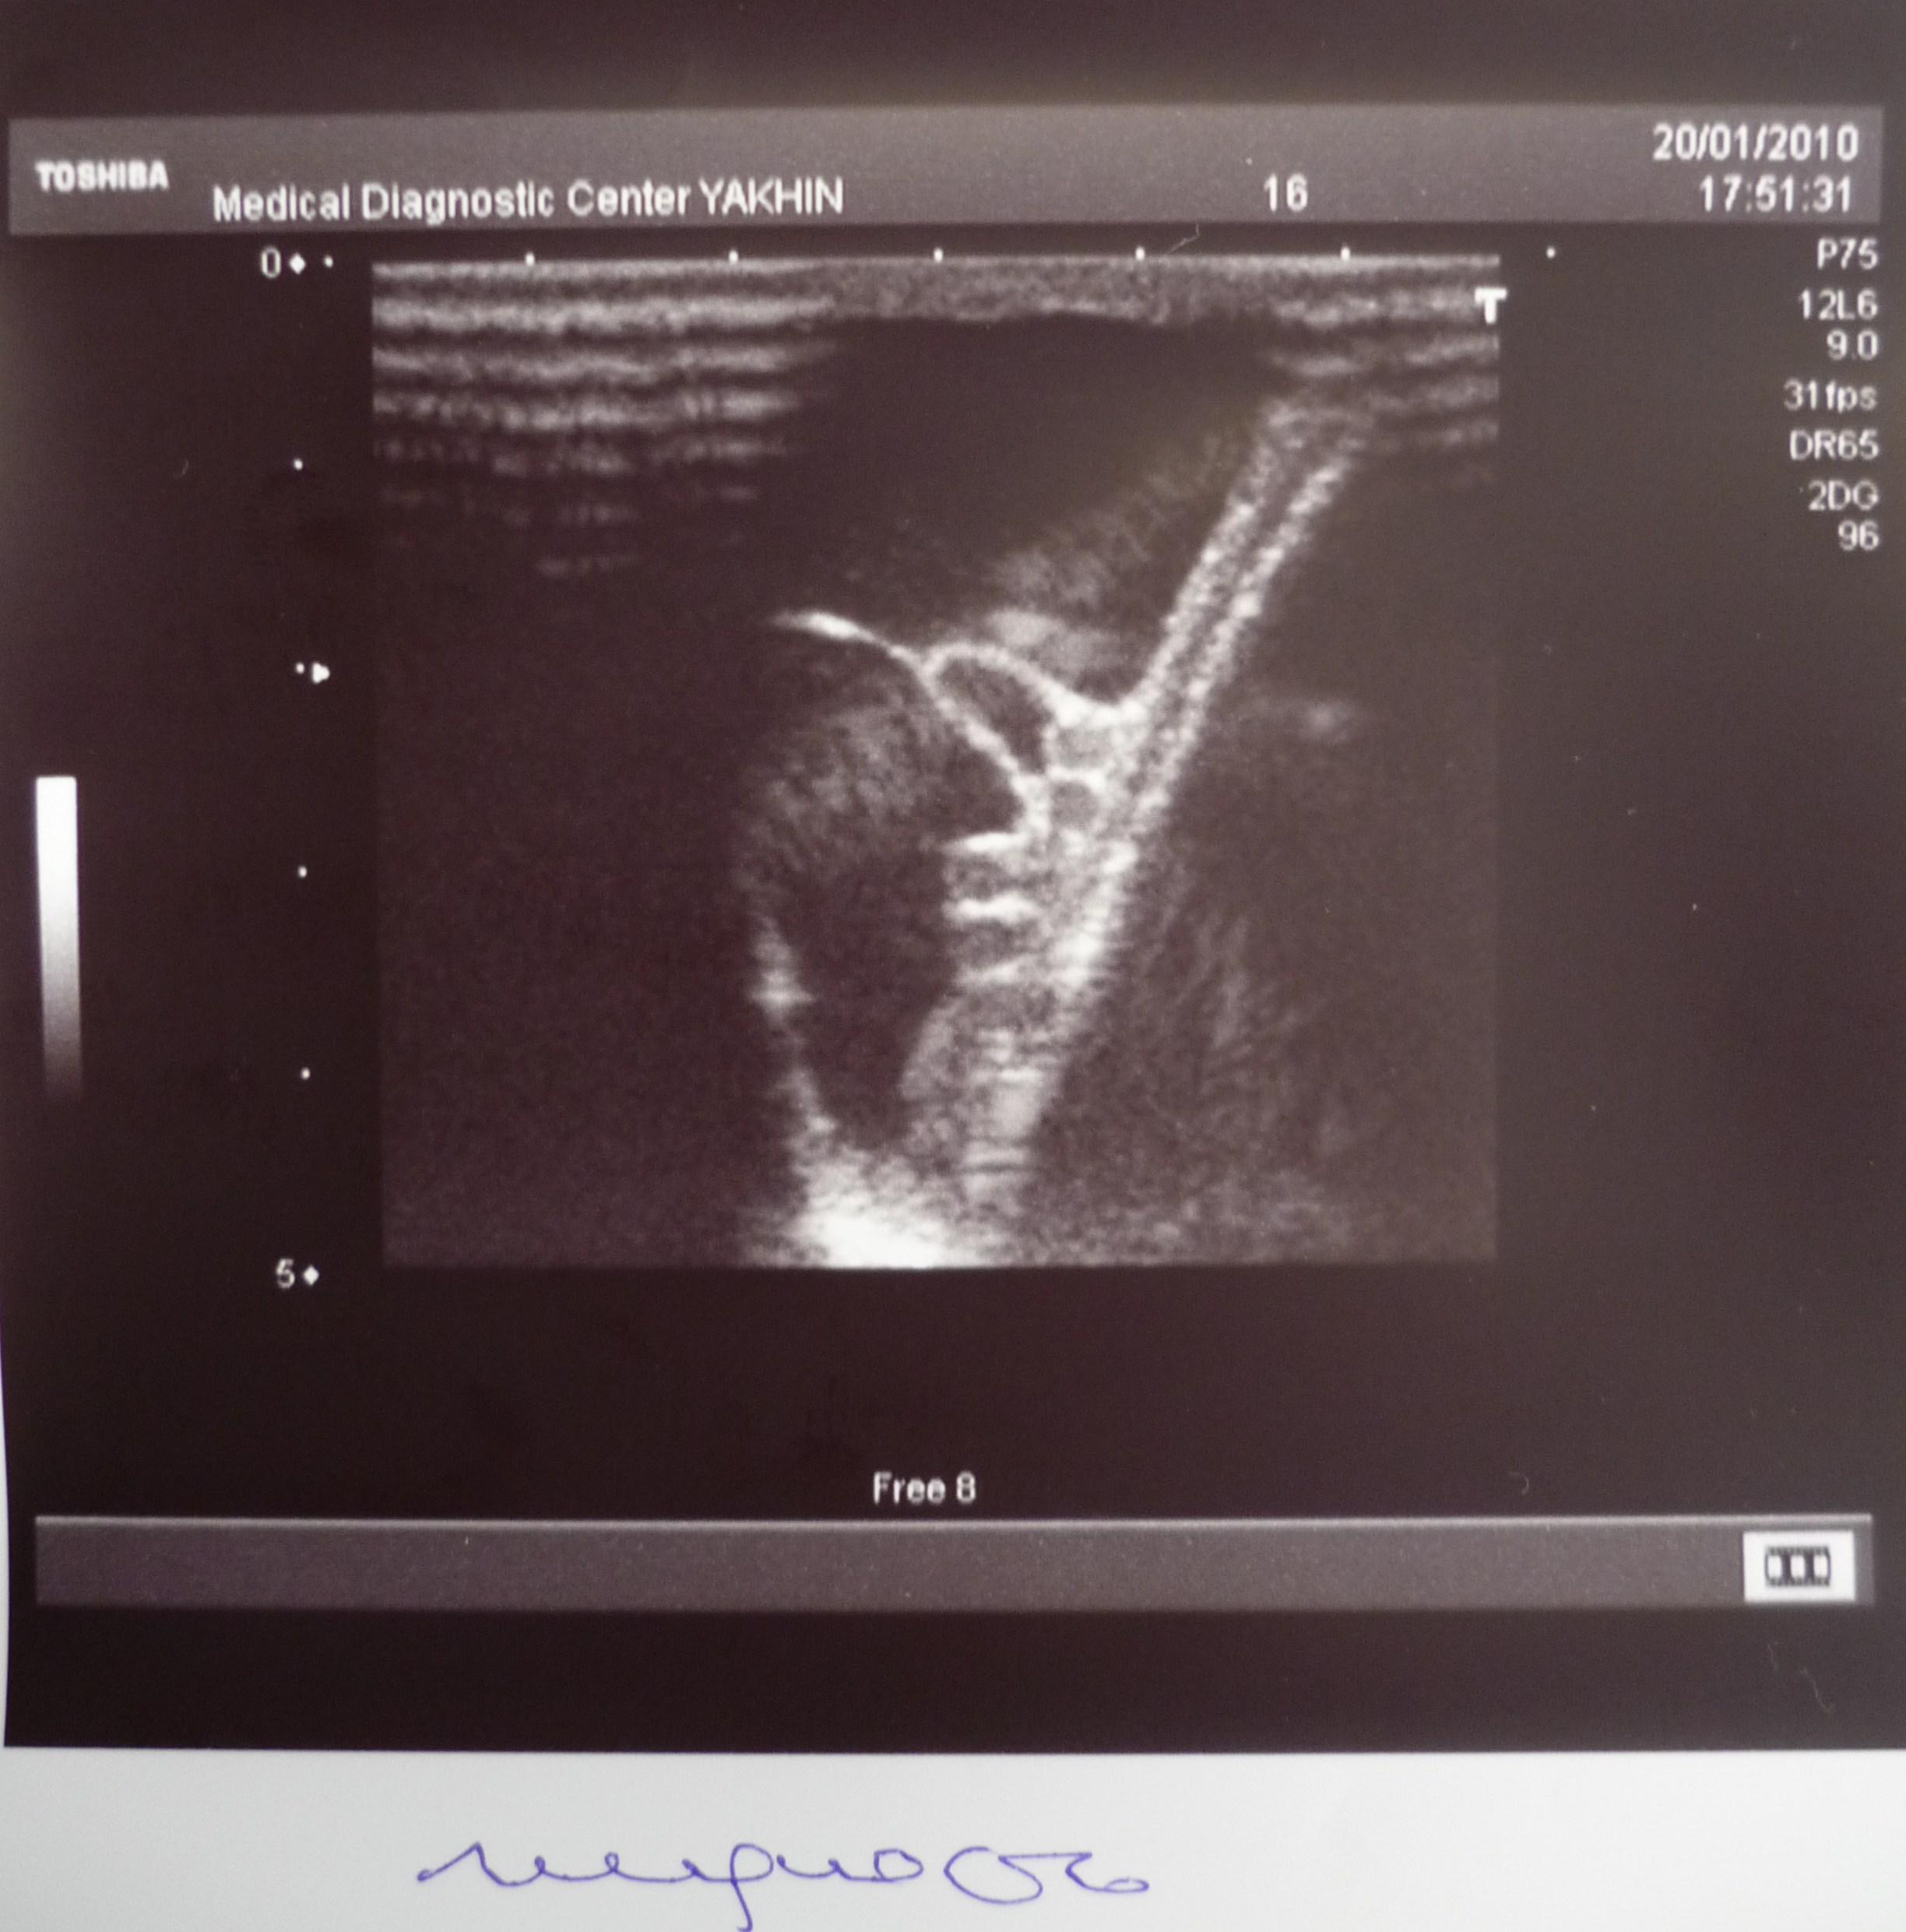

Здравствуйте! На днях сделал УЗИ органов мошонки с доплерографией. "Впечатлило". Три патологии сразу! Выраженное варикоцеле слева. Киста правого яичка. Водянка слева. Какими могут быть мои дальнейшие действия? Что посоветуете? Три операции сразу или же есть другие варианты? Обрекает ли это меня на бесплодие,есть ли возможность стать отцом?